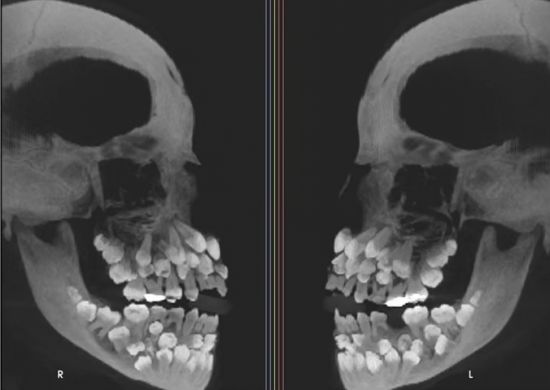

11세 소녀 입 안에서 치아가 무려 81개나 발견돼 학계에 충격을 주고 있다. 지난 15일 VN익스프레스 등 외신은 브라질에 사는 11세 소녀가 위쪽 유치 1개를 뽑기 위해 병원을 찾았는데 엑스레이 촬영 결과 소녀의 입안에서 유치 18개와 영구치 32개, 과잉치 31개 등 총 81개 치아가 발견됐다고 보도했다.

연구팀은 정밀 영상 검사를 통해 치아의 정확한 위치를 파악하고 유전 질환과 연관된 것은 아닌지 확인하기 위해 관련 유전자 검사도 함께 진행했다. 보통 다발성 과잉치는 쇄골두개이형성증, 가드너 증후군, 구개열 등을 동반하는 경우가 많지만, 검사 결과 소녀는 이 질환들에 해당하지 않았다.

추가로 진행된 염색체 검사에선 9번 염색체 일부 구간이 뒤바뀌는 구조 이상(염색체 역위)이 발견됐다. 드물게 나타나는 유전적 변이지만 과잉치 발생과 직접적 관련이 있는지는 알 수 없다고 연구팀은 전했다. 일부 과잉치는 잇몸 속에 깊이 묻혀 있거나 정상 치아와 형태가 유사해 정확한 구분이 쉽지 않다. 무작정 발치할 경우 턱뼈 손상 우려도 있다. 이에 연구팀은 치과 교정과, 악안면외과, 치주과, 보철과 등 여러 전문의와 팀을 꾸려 장기적인 치료 계획을 세우고 있는 것으로 전해졌다.